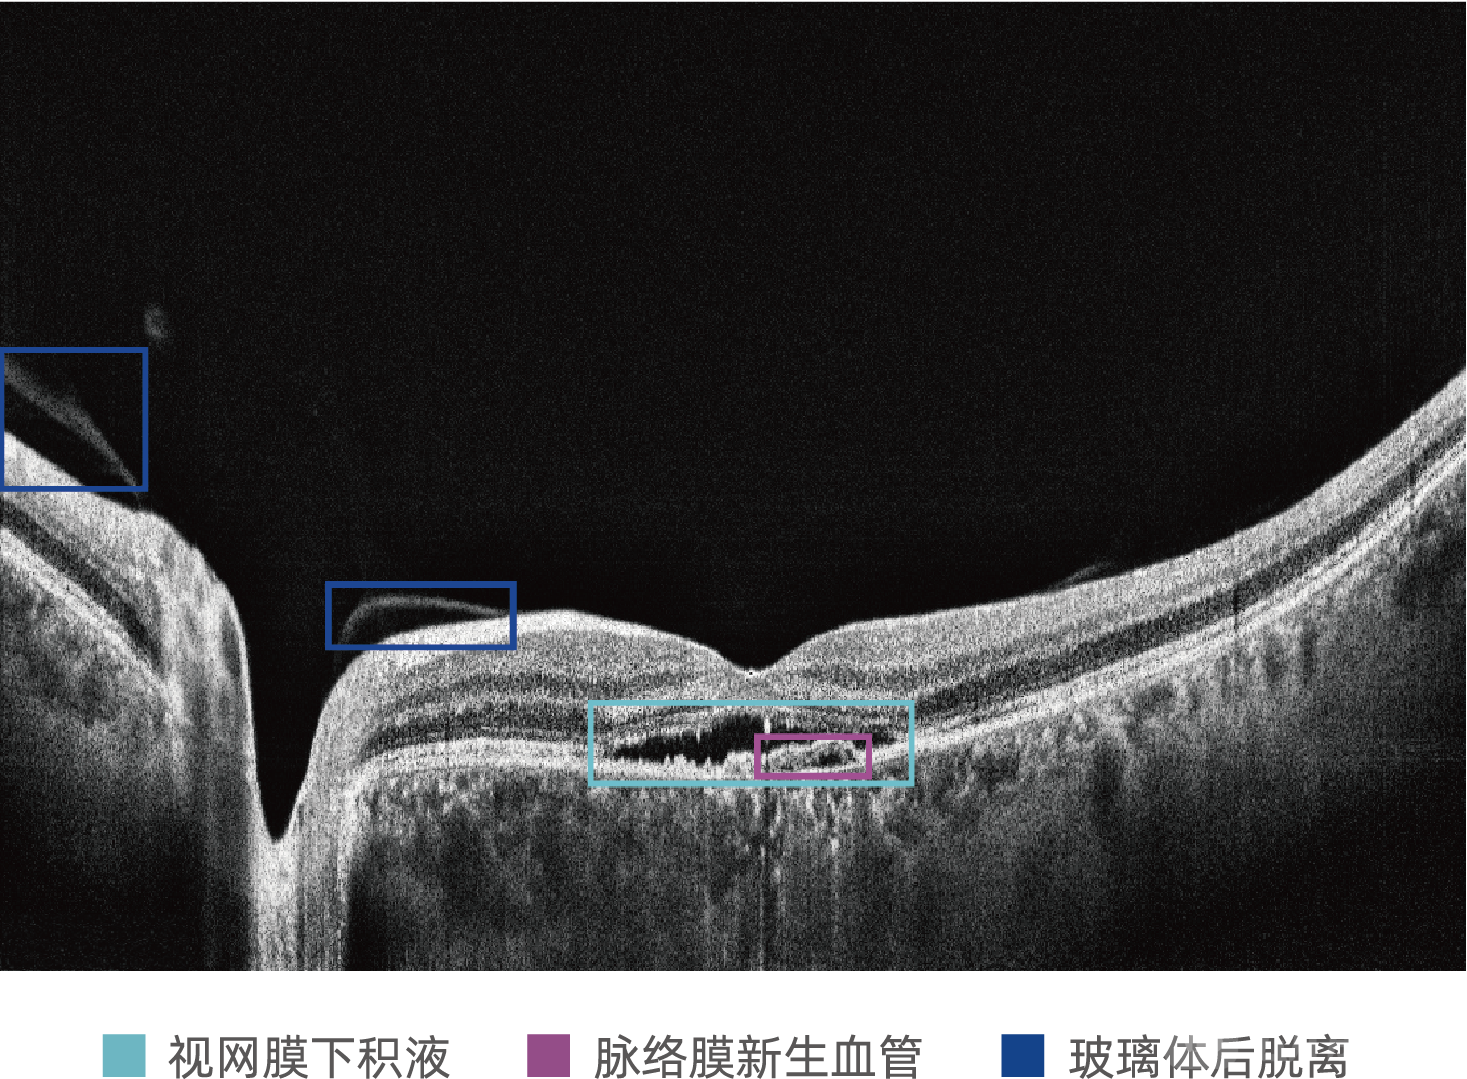

MIAS-3000使用比格威OCT设备采集图像,范围为12 X 9mm,可同时覆盖黄斑与视盘部位;MIAS-3000通过深度学习算法,自动分析OCT切片图像,精准识别玻璃膜疣、积液、新生血管等病灶信息,为50岁及以上患者提供是否存在中期及中期以上年龄相关性黄斑变性的辅助诊断建议。

案例1